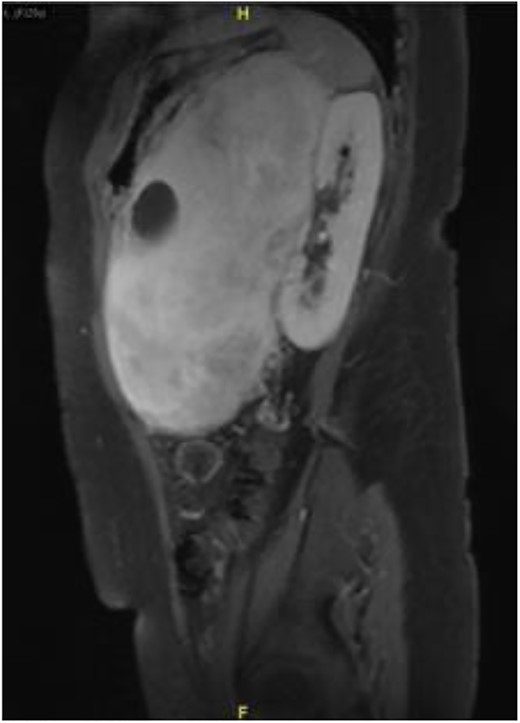

Subsequently, a magnetic resonance imaging was performed to better delineate fat plane with adjacent organs. Similarly, it showed a large left retroperitoneal solid-cytic mass with mass effect and poor fat plane between it and the left kidney, left adrenal gland, splenic hilum and pancreas. Additionally, posteromedially, the mass appeared to be abutting the abdominal aorta at L2 level with poor fat plane in between. Fortunately, no obvious invasion or filling defect was noted within (Fig. 2).